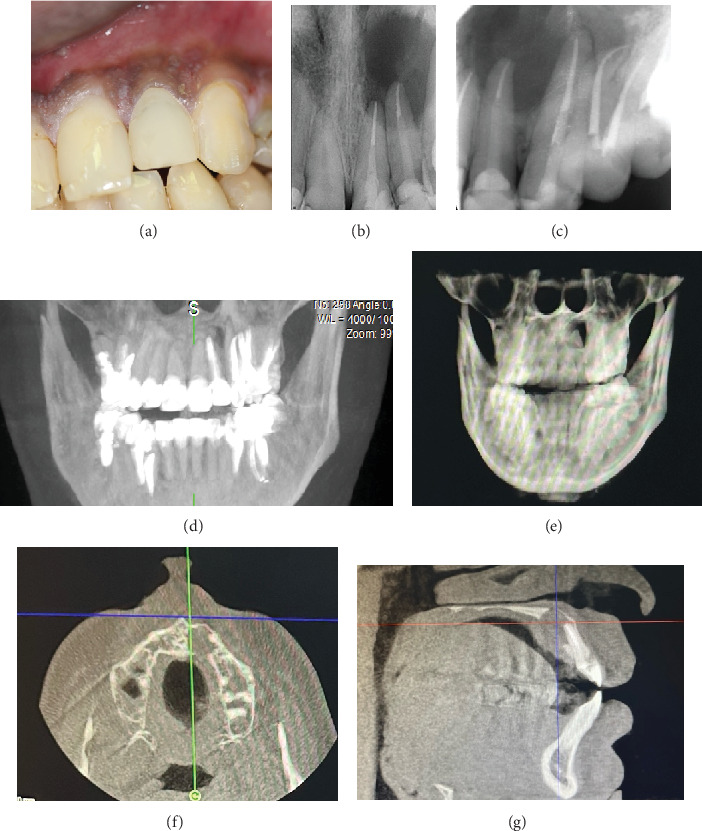

穿透性病变的致病过程导致两个皮质板的侵蚀和丧失。牙髓显微手术(MS)与骨移植物和膜放置(引导组织再生(GTR))是建议的治疗这种情况。这篇文章的目的是讨论一个不寻常的治疗方案,大的贯通病变不使用骨移植或膜。一名26岁的空军飞行员在高海拔地区旅行,因21号、22号和23号牙齿左上前病变引起的疼痛和肿胀到牙髓科就诊。经过彻底的临床检查、病史、临床和放射学检查,诊断出与先前治疗过的牙齿有关的全面病变。由于其工作性质,治疗方案包括不使用GTR的牙髓质MS。在3年多的时间里,常规随访对追踪受损区域的愈合过程至关重要,最终导致完全恢复。该病例强调了获得全面的病史和使用多学科方法诊断和处理全面病变的重要性,并取得积极的结果。

The pathogenic process of through-and-through lesions leads to erosion and loss of both cortical plates. Endodontic microsurgery (MS)with bone graft and membrane placement (guided tissue regeneration (GTR)) is the proposed treatment for such cases. This article is aimed at discussing an unusual treatment protocol for a large through-and-through lesion without the use of bone grafting or membrane. A 26-year-old Air Force pilot traveling at high altitudes presented to the Endodontic division for management of pain and swelling related to the upper left anterior lesion concerning Teeth #21, #22, and #23. Following a thorough clinical examination, medical history, and clinical and radiographic examination, the diagnosis of the presence of a through-and-through lesion related to previously treated teeth. The treatment plan included endodontic MS without the use of GTR due to his work nature. Over 3 years, routine follow-ups were essential for tracking the damaged area's healing process, which ultimately resulted in full recovery. This case emphasizes how crucial it is to obtain a thorough history and use a multidisciplinary approach to diagnose and manage through-and-through lesions, achieving positive outcomes.